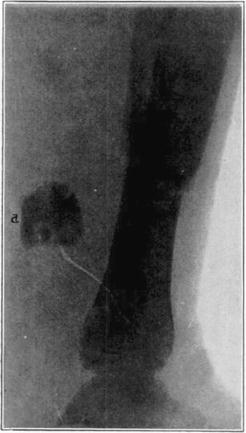

Case 4. Large splinter (a) displaced into soft parts from fresh fracture of tibia.

Case 4. The same (a) seven years later, showing reduction in size of splinter and apparent replacement by very spongy new bone.